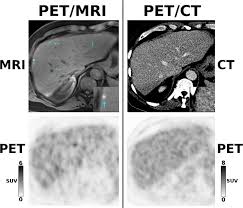

Bone scans, positron emission tomography (pet), and computed tomography (ct) all continue to be employed alone or in combination for the detection of breast cancers suspected to have spread. Pet/ct scans using axumin tracer, approved by fda last year and newly approved by medicare in some areas, are starting to be done at different locations. In a ct scan, you can see the broad pictures of all tissues and organs present in the body. Very subtle changes in tissue architecture are apparent on a mammogram, as are small deposits. A pet/ct scan is a newer technology used to create images of the body's cells as they work. After detecting the location of the tumor, the area will be biopsied for testing in the lab. This test can help show if the cancer has spread to your bones. At left is a ct scan, while the center image is from a pet scanner. Pet scan for breast cancer a positron emission tomography (pet) scan is an imaging test that uses a radioactive substance (called a tracer) to look for potential spread of breast cancer. A positron emission tomography scan is known as a pet scan. It can be done along with a ct scan. However, the pet scan uncovers every unusual activity in the body and is more sensitive than any other existing imaging test. Before a pet/ct scan, an iv that injects a small amount of a radioactive substance will be placed into one of your veins.

Pdf The Role Of Pet Ct For Evaluating Breast Cancer from www.researchgate.net This tracer can help identify areas of cancer that an mri or ct scan may miss. A positron emission tomography scan is known as a pet scan. Its supposed to be more sensitive/specific than naf and other older scans, and comparable i think to choline or acetate (lots of studies and info on the web) and. It can be done along with a ct scan. It is common for patients to receive a diagnosis for cancer of unknown primary. Normally, a pet scan is not used for breast cancer screening. Bone scans, positron emission tomography (pet), and computed tomography (ct) all continue to be employed alone or in combination for the detection of breast cancers suspected to have spread. Pet scans can be useful for evaluating people after breast cancer has already been diagnosed, in a number of different ways:

Pet scan is a type of test that may be used in cancer treatment. So i think in patients with breast cancer, it's very important to obtain both. Does anyone know if a ct scan can show breast cancer or colon cancer rather than the standard mammogram or colonoscopy? Another very common type of cancer is prostate cancer and for this type it's actually been proven that bone scans are more effective than pet scans. It can be done along with a ct scan. Pet/ct scans using axumin tracer, approved by fda last year and newly approved by medicare in some areas, are starting to be done at different locations. Am wondering if all the while we are getting ct scans for lung cancer, is this also scanning for. However, the pet scan uncovers every unusual activity in the body and is more sensitive than any other existing imaging test. Its supposed to be more sensitive/specific than naf and other older scans, and comparable i think to choline or acetate (lots of studies and info on the web) and. Thus, pet/ct detected a primary breast mass and metastatic lymphadenopathy that mammography and ultrasonography failed to detect a finding not previously reported, to our knowledge. But you might also just hear it called a pet scan. Pet scans can be used to determine how much cancer is in a person's body and how far the cancer has spread, which is called staging. And other kinds will show only on a bone scan but not a pet scan.